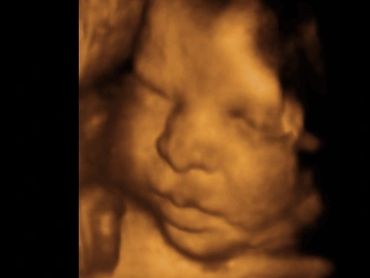

All our providers do their own ultrasounds in the office during your visit. We are known for our ultrasounds and do at least four with each pregnancy. And we can record your ultrasound on a USB device for you to take home and share!